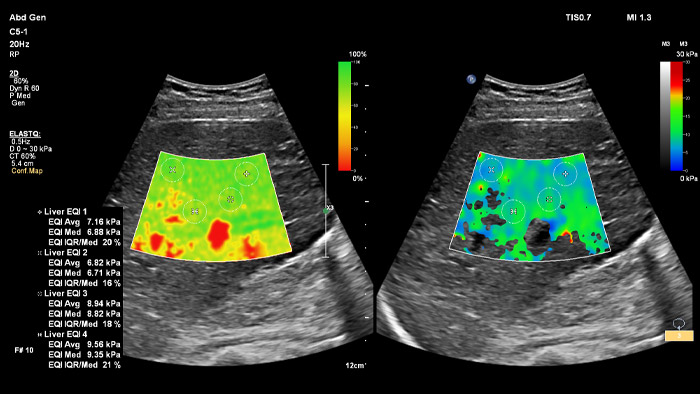

ElastQ bietet mit der 2D-Scherwellen-Elastographie (2D-SWE) eine nichtinvasive, reproduzierbare und einfach durchzuführende Echtzeit-Beurteilung der Gewebesteifigkeit. Außerdem beinhaltet ElastQ Imaging eine Funktion zur retrospektiven Messung an gespeicherten Bildern sowie eine entsprechende Darstellung der statistischen Sicherheit für die höchste Scherwellenausbreitung.

ElastPQ ist eine Punktscherwellen-Elastographie (pSWE) zur Gewinnung von Werten der Gewebesteifigkeit der Leber. Mit Hilfe von Echtzeit-Bildgebung wird die ROI über den relevanten Bereich gelegt und innerhalb von Sekunden werden die Daten zur Gewebesteifigkeit erfasst. Es können mehrere Abtastungen aufgezeichnet und in einem Leberbericht zusammengefasst werden.